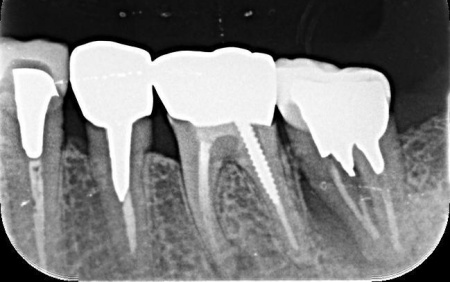

その後、歯科用CT撮影を行い、顎の骨の量や形、神経や血管の位置を立体的に確認しました。撮影したデータをもとに、インプラントを埋め込む位置や角度、深さについて事前に設計を行い、安全性と噛み合わせのバランスを考慮した治療計画を立てます。

後日、インプラント体と骨がしっかりと結合したタイミングで、インプラント体の上に土台を装着し、人工の歯を取り付けます。

また、治療期間中は定期的にレントゲン検査と口腔内の状態確認を行いました。

抜歯後の骨の状態を確認しています。

インプラント体と骨の結合を確認しました。